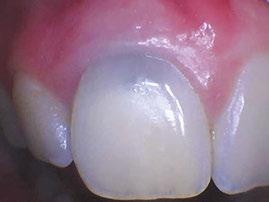

With trauma protocols, we recall these patients quarterly for the first year prepared to intervene with traditional endodontic treatment anytime we see evidence of failure. We then see these patients annually for 5 years, or more often, until I am satisfied that the root growth is complete. Unfortunately, I was starting to see an ugly silver gray halo at the cervical margin as a result of the tooth erupting out of the alveolus as part of the normal growth of the child. All of a sudden, I was faced with another treatment challenge. Now I had to take out my minimalistic composite, remove MTA, and then remove tooth structure to facilitate non-vital bleaching. I remember being very frustrated that we were weakening tooth structure coronally after working so hard to grow the root. I also faced the possibility of damaging the pulp as we had to remove much of that 2 mm MTA cap.

Enter EndoSequence®. I remember my Brasseler rep coming to my office to fulfill my bur order. He asked me if I was familiar with this new bioceramic root repair material in a putty consistency. It has all the desirable qualities of my original MTA but also was the answer to my problems. Now there was a material which had amazing handling properties, did not require pre-mixing, and would bond to dentin because of its hydrophilic properties and very small particle size. A huge benefit was that it would not stain the dentin. At first being a purist, I was reluctant to change because I was so hooked on the benefits of my original MTA. I started using it first in my posterior apexogenesis cases where color was not a concern.

Figures 1 and 2: Example of staining from traditional MTA, non-vital bleaching after Figure 3: Pre-op Figures 4 and 5: Pulp cap Figures 6: Apexogenesis